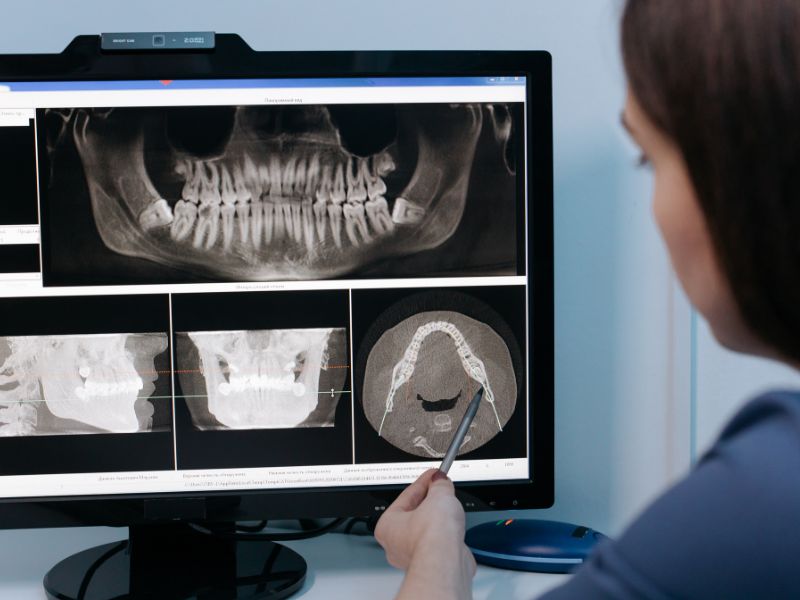

Getting a dental X-ray is essential for understanding what’s happening beneath the surface of your gums and teeth. These images help detect issues that aren’t visible during a standard check-up. From cavities forming between teeth to impacted wisdom teeth or bone loss, dental x-rays allow for early diagnosis and better treatment planning. Despite their importance, many people feel hesitant due to safety concerns or uncertainty about the process. This article explores what you should know before stepping in for your next dental X-ray, and how it can directly impact your oral health journey.

Getting a dental X-ray is most helpful when your dentist needs to investigate pain, plan treatment, or check for structural problems that can’t be seen otherwise. It becomes an essential tool for identifying what’s really going on—and choosing the most effective path forward. Here are the situations where dental X-rays are most beneficial:

- Before major dental procedures, like implants or extractions, to evaluate bone density and root placement.

- During routine check-ups, especially if you’re prone to decay, gum disease, or have a history of dental issues.

- When experiencing unexplained discomfort, like headaches or jaw pain, to rule out hidden causes.

- For orthodontic planning, to assess tooth position, growth patterns, and jaw development in younger patients.